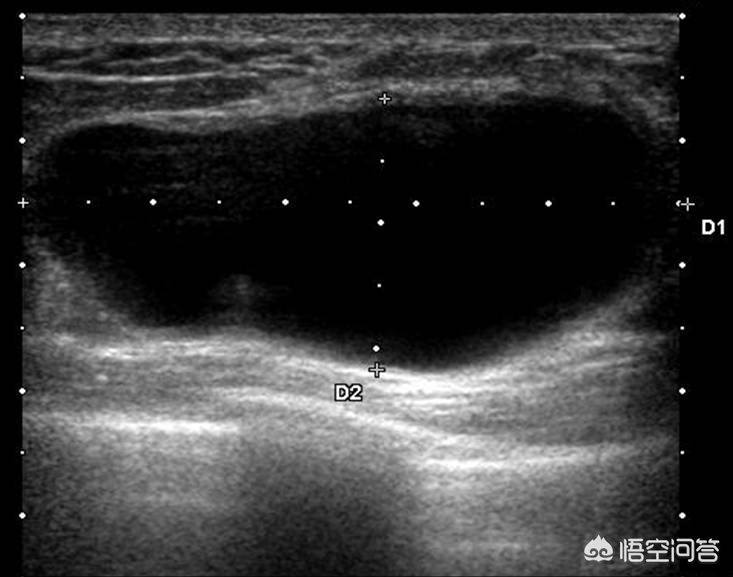

乳腺囊肿是***的囊性结节,在B超下是一个没有回声的暗区,边界清楚,没有血流信号。如下图示:乳腺囊肿是一个无回声的结节。